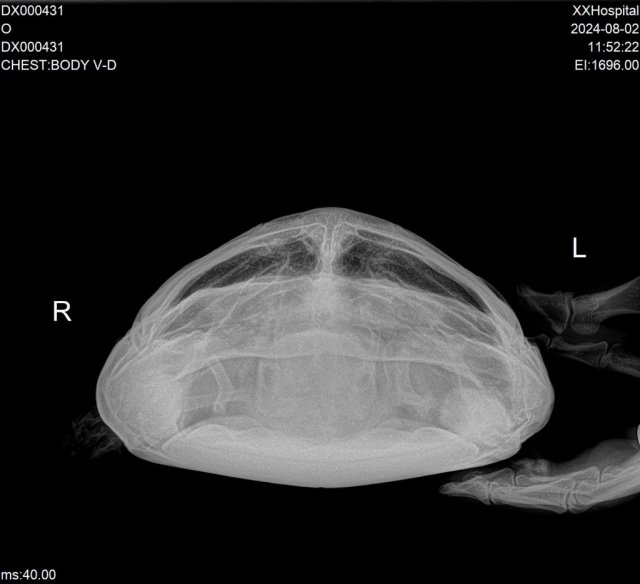

Консультанты moth Ваше имя: Мария Локация: Москва Опубликовано: 31 июля 2024 Консультанты Опубликовано: 31 июля 2024 @Алеся Панкова Дитрим точно колоть больше не нужно сейчас любой препарат, тем более в неверной дозировке, может в принципе её добить. И держать черепаху сейчас нужно вне аквариума, иначе опять утонет - посадите пока в контейнер без воды на влажные полотенца. Да, нужен рентген, чтобы проверить что с лёгкими и желудком, почему не смог всплыть. По фото у черепахи сильный провал панциря и отёкшие глаза - это признаки сильного авитаминоза и хронического дефицита кальция. Рентген если поедете делать - нужно минимум две проекции: под номером 1 и любая 2 или 3, но лучше 3.

Алеся Панкова Ваше имя: Газ Локация: Минская обл г Вилейка Опубликовано: 2 августа 2024 Автор Опубликовано: 2 августа 2024 Здравствуйте, все отменила.Сделала ренген.

Консультанты moth Ваше имя: Мария Локация: Москва Опубликовано: 2 августа 2024 Консультанты Опубликовано: 2 августа 2024 @Алеся Панкова если финансы позволяют - возьмите онлайн консультацию у любого ветеринара из списка https://cherepahi.ru/servisy/konsultatsii/ кроме Бойцовой, она сейчас долго отвечает. Из того, что я вижу - есть помутнение в лёгких (инфекция) и снижена плотность костей, нужно чтобы внимательно посмотрел именно врач и назначил правильное лечение. Если нет - напишите, я распишу лечение как я вижу, но в интересах черепахи обратиться именно ко врачу, т.к. тут случай очень серьёзный